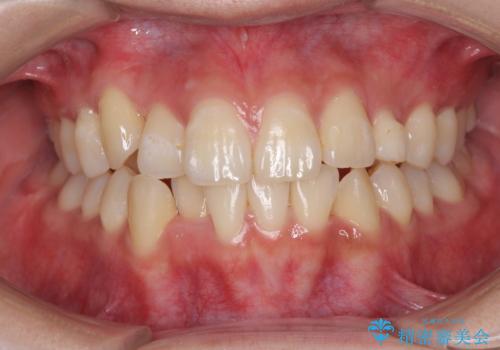

- 前歯のデコボコと残っている乳歯の部分へのインプラント治療を希望して来院された患者様です。

当初は目立たない上下裏側矯正を希望されていましたが、歯並びの悪さによる磨き残しが多く、歯肉炎が認められたため、より清潔な環境で治療を進められるインビザラインを選択することとしました。

歯並びが整ったことで治療前に認められた歯肉炎は全くなくなり、患者様には大変満足していただきました。